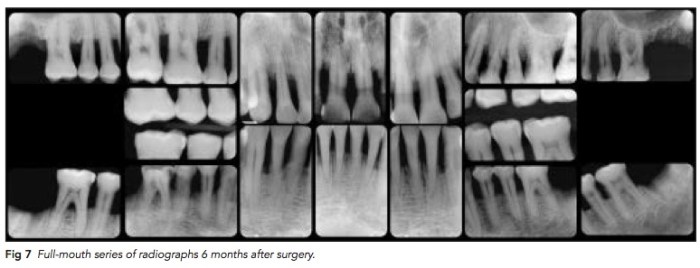

使用的是sulfonic/sulfuric acid solution (HYBNEX, EPIEN Medical), 方法就是將酸打進去pocket裏面30秒, 然後用水沖掉. 這次做了5個case, 基本上只有一開始打藥劑時會痛, 但是之後組織脫水變白後會慢慢回復. 疼痛指數還可接受而發炎的反映在大約一周就會消失.

我覺得這樣的方法比較像是用火摧毀雜草, 然後再長回來. 但是這樣的做法是否真的有效, 需要更長期的評估追蹤.